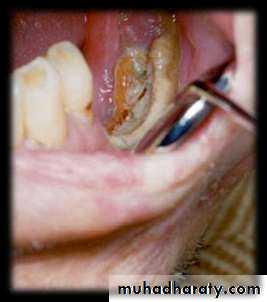

• Mandible is more prone than maxilla as vascular supply is readily compromised.• Cropped panoramic radiograph of suppurative osteomyelitis at the right side of mandible.

• ACUTE SUPPURATIVE OSTEOMYELITIS

• Organisms entry into the jaw, mostly mandible, compromising the vascular supply• Medullary infection spreads through marrow spaces

• Thrombosis in vessels leading to extensive necrosis of bone

• Lacunae empty of osteocytes but filled with pus , proliferate in the dead tissue

• Suppurative inflammation extend through the cortical bone to involve the periosteum

Stripping of periosteum comprises blood supply to cortical plate, predispose to• further bone necrosis

Sequestrum is formed bathed in pus, separated from surrounding vital bone